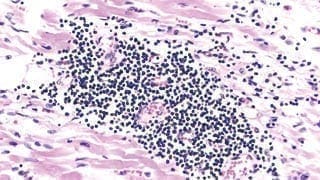

Zugrunde liegt dem Flimmern meist eine Vergrößerung der Vorkammern mit Einlagerung von Bindegewebe. Dies kann dazu führen, dass sich die Ströme nicht mehr normal ausbreiten können. Hinzu kommen meist durch Umbauvorgänge der Muskulatur der Vorhöfe zusätzliche elektische Impulse Elektrische aus den sog. Lungenvenen. Diese werden auf die Vorkammern übertragen und führen zum Flimmern.

Umbauvorgänge in der Muslulatur der Vorkammern und Impulse aus den Lungenvenen führen zu Vorhofflimmern